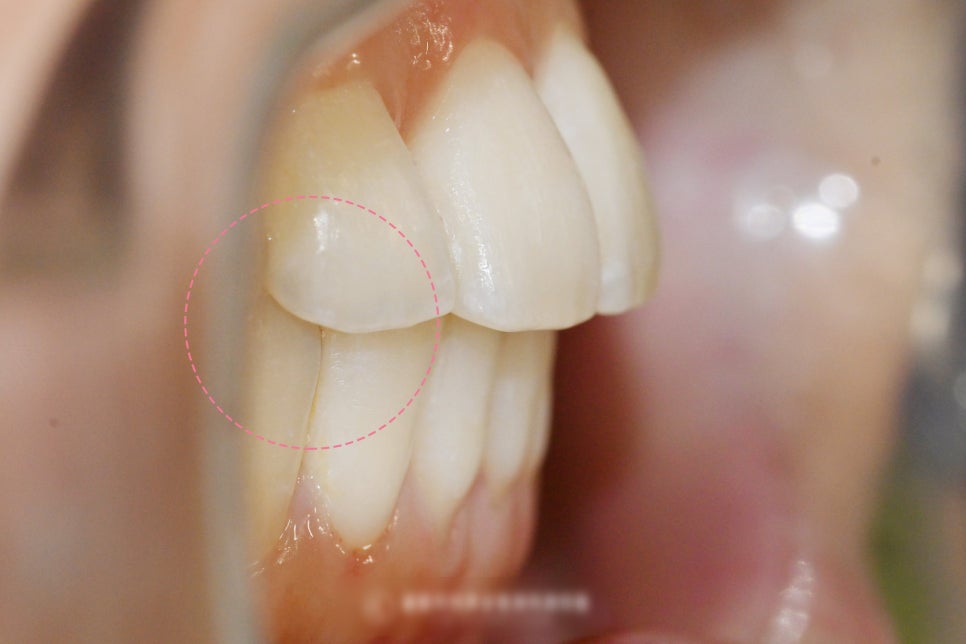

오른쪽 아래 43번 송곳니를 기준으로

맞닿는 위쪽과의 관계를 보면

앞니 교합이 떠있는 것이 확인 됩니다.

이렇게 맞지 않는 앞니 교합을 가질 경우에는

추후 생길 수 있는 네거티브들이 많습니다.

특정한 치아에 교합력이 몰리게 되며,

이에 따라서 특정 치아의 수명이

급격히 짧아지는 부작용을

초래할 수 있습니다.

조금 더 나아가 TMJ(턱관절)에도

부정적 영향을 줄 가능성이 있습니다.